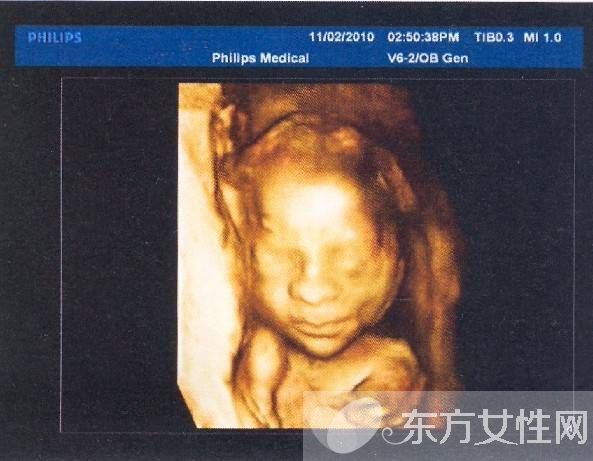

普通B超和彩色B超都是二维平面图像,这两种技术仍在使用,但由于观测效果较为依赖羊水量和胎儿体位,一旦在怀孕晚期羊水减少或者胎儿面向母亲的背部,观测效果就不太理想。而且,二维图像不能满足准妈妈们“看到”宝宝模样的愿望。因此,最近几年,随着计算机技术的发展,又出现了三维B超,也就是将二维图像合成模型,透过屏幕可从各个方位观察胎宝宝。

三维彩超、四维彩超的图像是后期生成的,并不是说观察到的图像就是三维、四维的,而是仍然用普通彩超观察,然后通过仪器中的转换软件将观察到的平面图像转成三维、四维的立体图像,使不懂B超图像的人也能看出胎儿的模样。而三维和四维的区别就在于在一个“时间维”,也就是说,前者是图片,后者是录像,可以让孕妈妈看到胎儿一连串的动作。